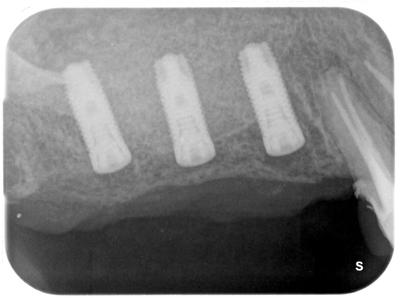

2次オペ時

インプラントカバースクリュー上部まで骨が造成している。

真ん中のインプラント上部の骨を一部慎重に除去した状態。